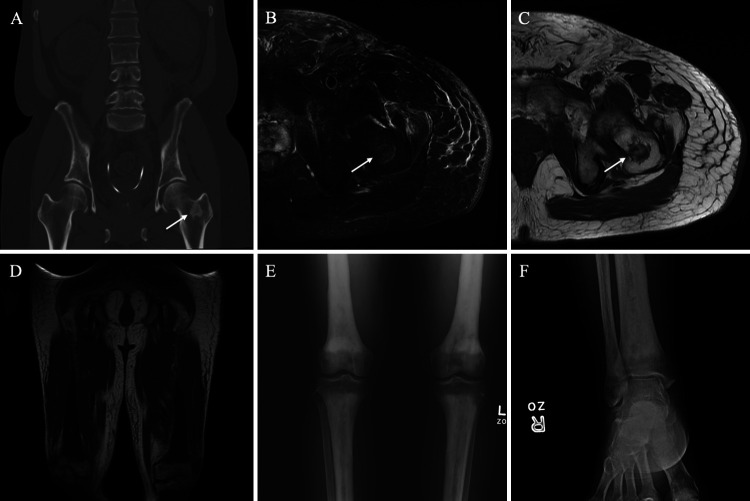

FIG. 5.

Erdheim-Chester disease skeletal changes. Coronal CT (A) shows a 2.0-cm sclerotic lesion in the left femoral neck (arrow). Axial T2WI with fat saturation (B) and axial T1WI (C) show a T2-hyperintense and T1-hypointense irregular lesion (arrows) centered at the left femoral neck corresponding to the CT finding. Coronal T1WI (D) shows diffuse symmetric T1 hypointensity involving bilateral mid-distal femurs and proximal tibiae, sparing the epiphysis. A frontal radiograph (E) of the bilateral knees shows bilateral symmetric metaphyseal and diaphyseal sclerotic changes of the tibiae, fibulae, and femurs with epiphyseal sparing. A frontal radiograph (F) of the right ankle shows similar sclerotic changes of the distal tibia and fibula, sparing the epiphysis. Symmetric findings were seen on the contralateral ankle. The constellation of findings is consistent with sclerotic changes secondary to ECD.